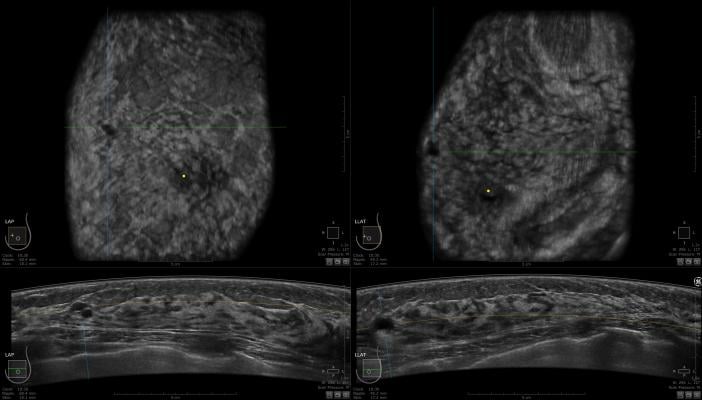

Liu and Fyles examined tumor specimens from participants in a prior randomized clinical trial who received either tamoxifen (hormone therapy) plus whole-breast radiation therapy, or only tamoxifen.

The research team analyzed molecular biomarkers in these samples, which were then classified into six subtypes. The results demonstrated that women in the luminal A subtype had the best outcome, with a 10-year risk for local relapse of 8 percent with tamoxifen alone versus 4.5 percent with both tamoxifen and radiation.

Luminal A is defined as ER-positive, PR-positive, HER2-negative and low Ki-67 (an indicator that breast cancer cells are slowly growing, dividing or proliferating).